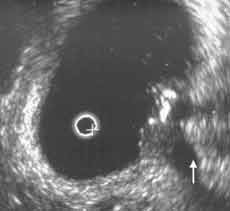

Рис. 7 и 8. Цистэндосонограммы. (Слева) Рак мочевого пузыря с врастанием в интрамуральный отдел мочеточника (стрелкой указан расширенный мочеточник). (Справа) Рак шейки матки с врастанием в мочевой пузырь.